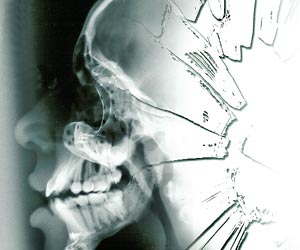

X-rays are electromagnetic radiations in a wave form just like gamma,ultraviolet,infrared and radio waves but with a different wavelength. X-rays,for instance,can pass through wood and the human body just like light can pass through glass, says Dr Sneh Bhargava,radiologist,Sitaram Bhartia Research Institute,New Delhi.